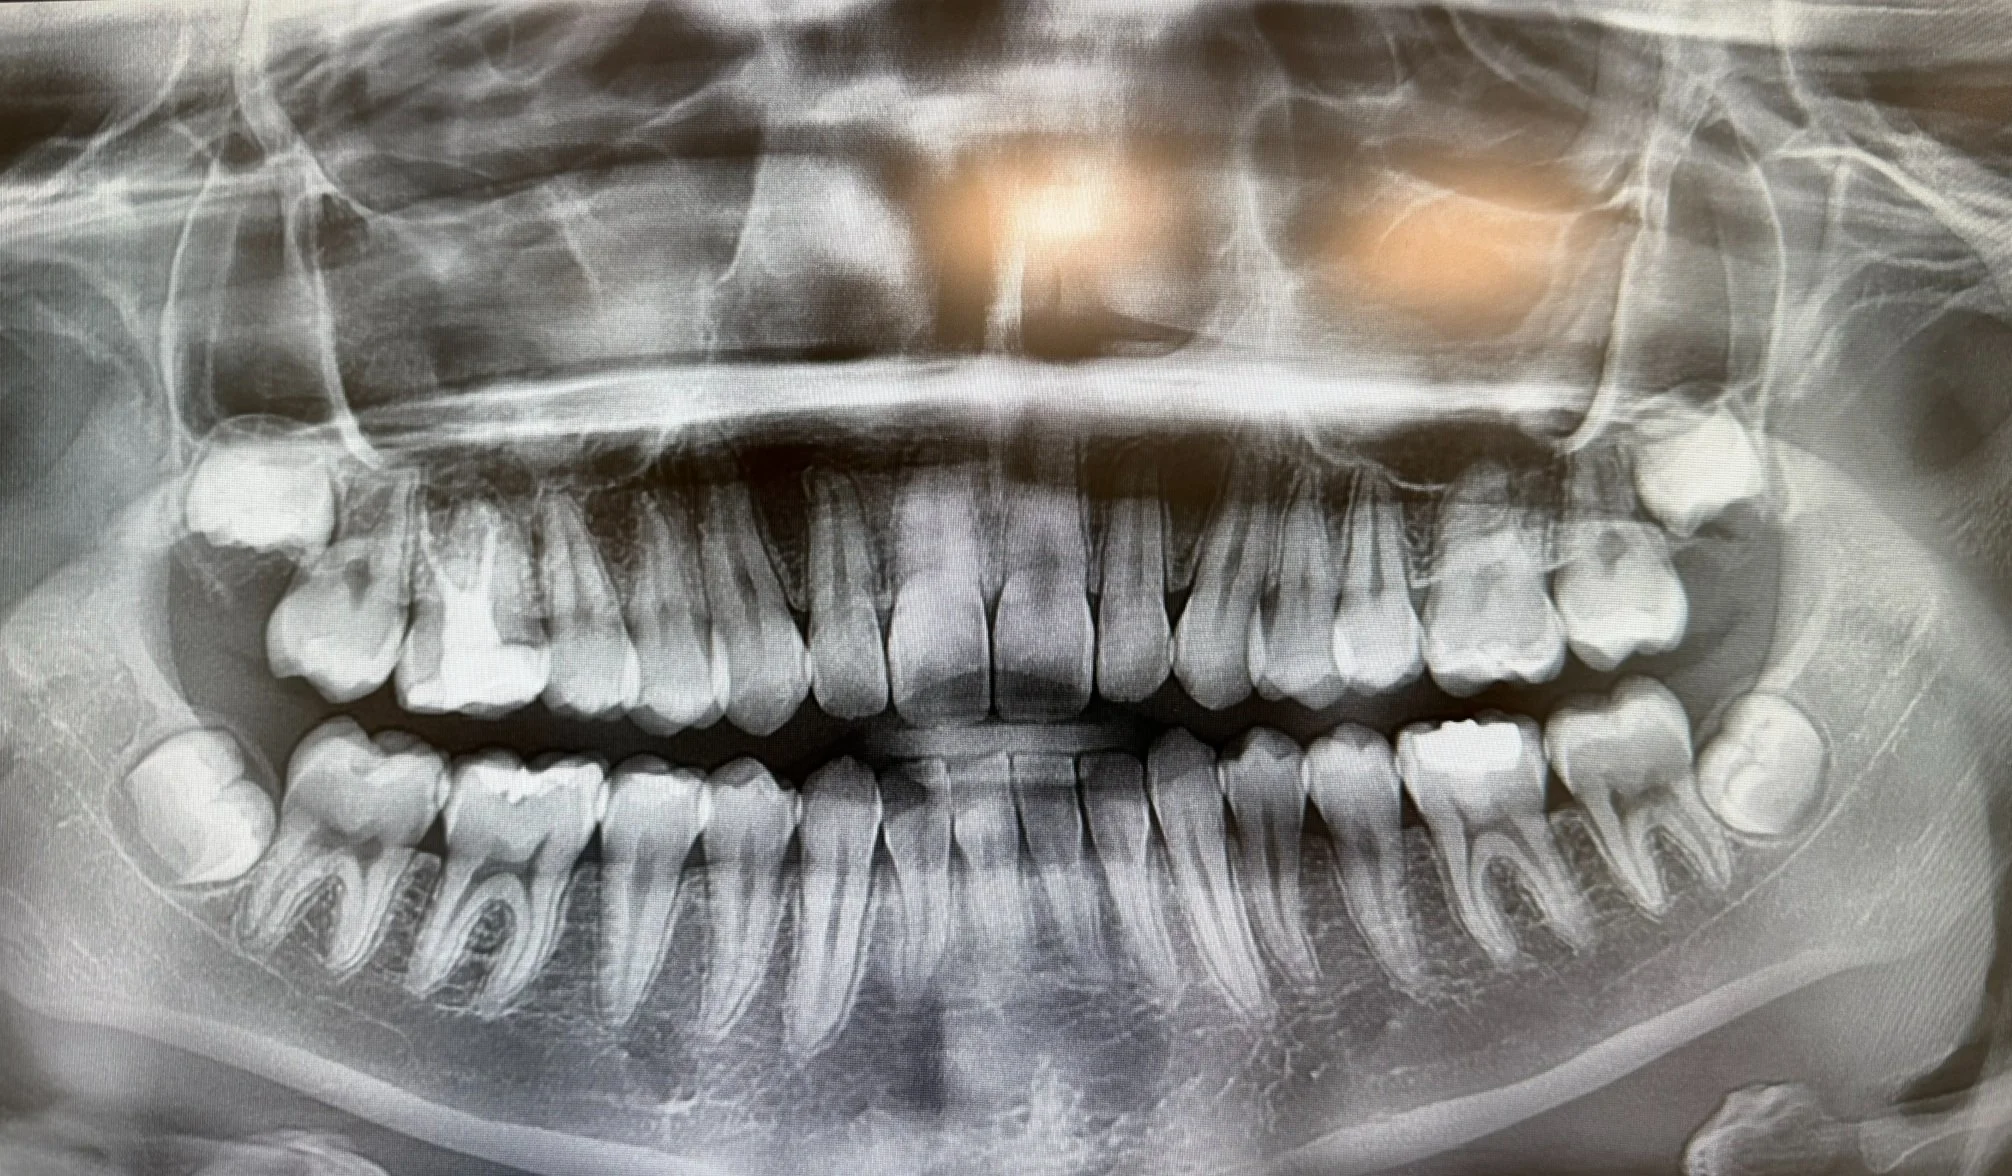

When this patient visited the clinic, both lower wisdom teeth were deeply impacted and positioned horizontally inside the jawbone. As seen in the pre-operative X-ray, the teeth were pressing against the second molars and located close to the nerve canal — a situation that often causes anxiety due to the risk of swelling, pain, or nerve injury.

The after X-ray confirms:

• Complete removal of the impacted teeth

• Preserved bone integrity

• Safe distance from the nerve canal

• No surgical complications